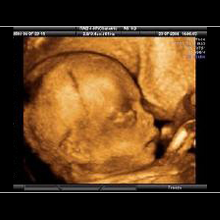

Eine ganz besondere Faszination bieten die neuen 3D/4D Ultraschallgeräte.

Die 3D-Sonografie erlaubt die einzigartige räumliche Darstellung des ungeborenen Kindes. In der 4D-Technik werden Bewegungsabläufe in nahezu fotorealistischer Weise in Echt-Zeit (Real-Time) mit bis zu 25 Bildern/sec. möglich- ein faszinierender Einblick in die Welt des Ungeborenen.

HIER EINE AUSWAHL VON 3D-ULRASCHALL-BILDERN: